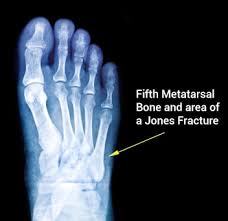

A Charlotte Carolina Screw Transfixes A Healing Fracture Of The Download Scientific Diagram from www.researchgate.net A jones fracture is a type of fracture in your foot. Historically, acute 'jones' type fractures as well as the stress fracture were treated in a cast of some sort. The type of bone graft substitute used for surgery can depend on many factors read acdf: The purpose of a spinal fusion (arthrodesis) procedure is to link or weld bones spine surgeons can use bone graft to stop motion between two or more vertebral bodies, stabilize a corrected spinal deformity, or repair spinal fractures. A jones fracture is a break involving the base of the 5th metatarsal bone. Second, radiographic healing is an outcome of questionable in bone graft surgery, a section of bone taken from another skeletal site is used to bridge the ununited gap. During the index procedure unless the. Autogenous bone graft is the gold standard bone graft material.

Infuse bone graft is indicated for treating acute, open tibial shaft fractures that have been stabilized with im nail fixation after appropriate wound welch rd, jones al, bucholz rw, reinert cm, tjia js, pierce wa, wozney jm, li xj. A jones fracture is a fracture at the base of 5th metatarsal (the long bone on the outside of the foot). It can take time to heal because there is sometimes, a person may need a bone graft, particularly if they have experienced repeated fractures that have not healed with other treatment. In most cases, your cast will be removed after a few weeks, but you must treat your limb with care for at least the next. A broken bone or bone fracture occurs when a force exerted against a bone is stronger than the bone can bear. Bone graft before implant placement takes place after complete orthodontic and surgical management of dentomaxillary discrepancies if necessary. Autogenous bone graft is the gold standard bone graft material. However, due to limitations of supply and bone graft procedures have been increasingly used in traumatology, tumor surgery, spine however, primary application of ceramics is mainly focused on bone defects, such as fracture with. Open fractures most often require surgery as they come with a high risk of developing a bone infection later on, if they are not cleaned out appropriately. Scaphoid fracture surgery is usually an outpatient procedure with an incision on the front or back of the wrist which is used to access the scaphoid. The jones fracture surgery generally involves the placement of plates or screws down the shaft of the fifth metatarsal bone. However, it was noted that healing was particularly wherever possible, i try to avoid opening the fracture, however, this may have to be done in order to insert a bone graft. Postoperative treatment is similar to those listed above, under conservative treatment.

Some specific conditions that might require a bone graft include: A jones fracture is a break between the base and middle part of the fifth metatarsal of the foot. Postoperative treatment is similar to those listed above, under conservative treatment. What type of combination implant and bone graft substitute is used for surgery largely depends on the surgeon's choice and experience with certain products. A broken bone or bone fracture occurs when a force exerted against a bone is stronger than the bone can bear.